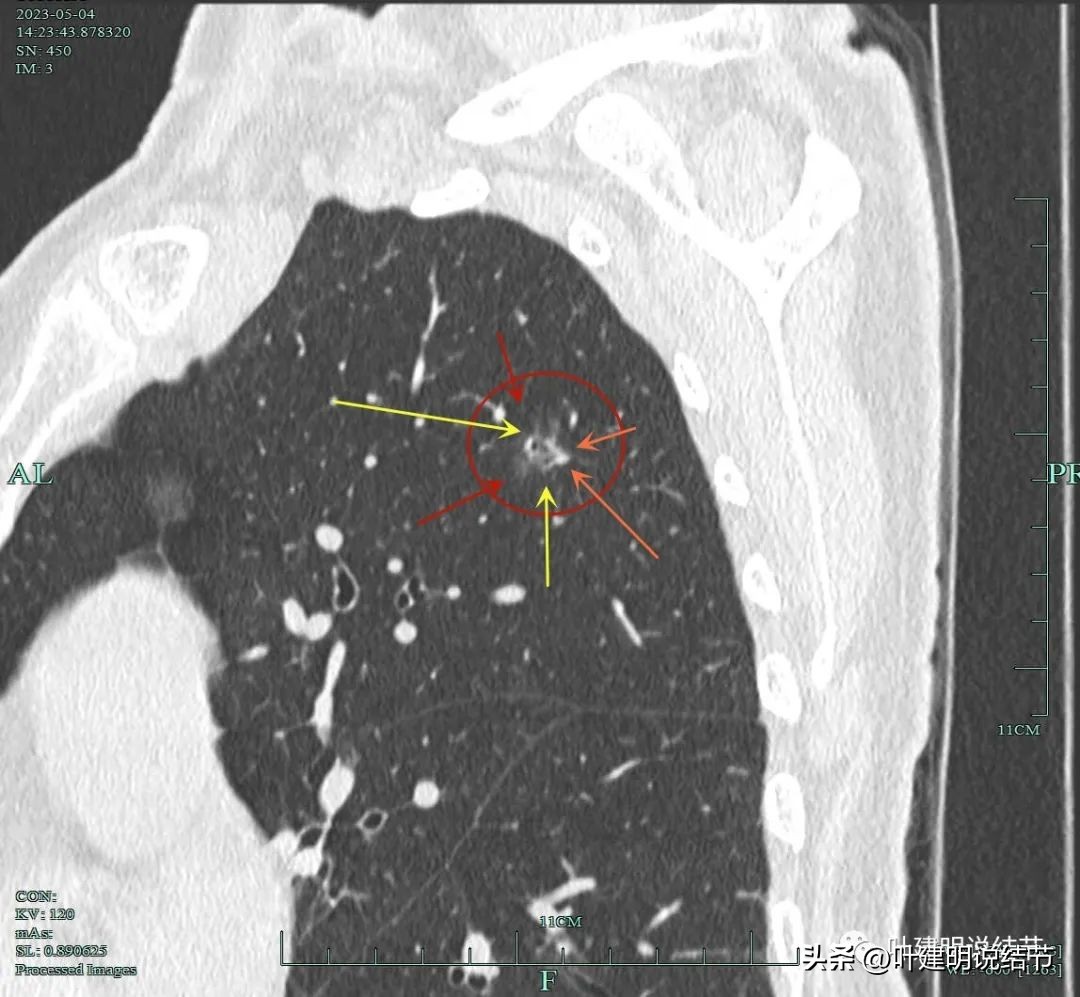

非薄层扫描显露右上叶略显模糊的磨玻璃结节,中间有小空泡的样子,边缘不平显得有毛刺样征,密度不均匀。

薄层显示病灶磨玻璃密度,内部有血管穿行,灶内有小空泡的样子,整体边缘轮廓较清。

灶内穿行的血管有异常增粗,且显得毛糙。灶内空泡样征是扩张的细支气管;表面不平,似有浅分叶的样子。磨玻璃部分密度较低。

上图显示血管进入病灶,进入后似乎就散掉了。

靶扫描重建发现病灶内部穿行血管毛糙,细支气管扩张,边缘毛刺样征。

灶内走行的血管模糊、异常增粗与毛糙。病灶总体轮廓较清,磨玻璃部分密度较低。

上图显示明显的血管弯征。而且磨玻璃病灶密度欠均匀。

病灶分叶、细支气管扩张,微小血管进入;整体轮廓较清。

上图这个视角清楚显示灶内的空泡征是扩张的细支气管。而且灶外细些,灶内更远离肺门,反而扩张,说明病灶有牵拉力呀!

边缘有毛刺征,灶内密度欠均。